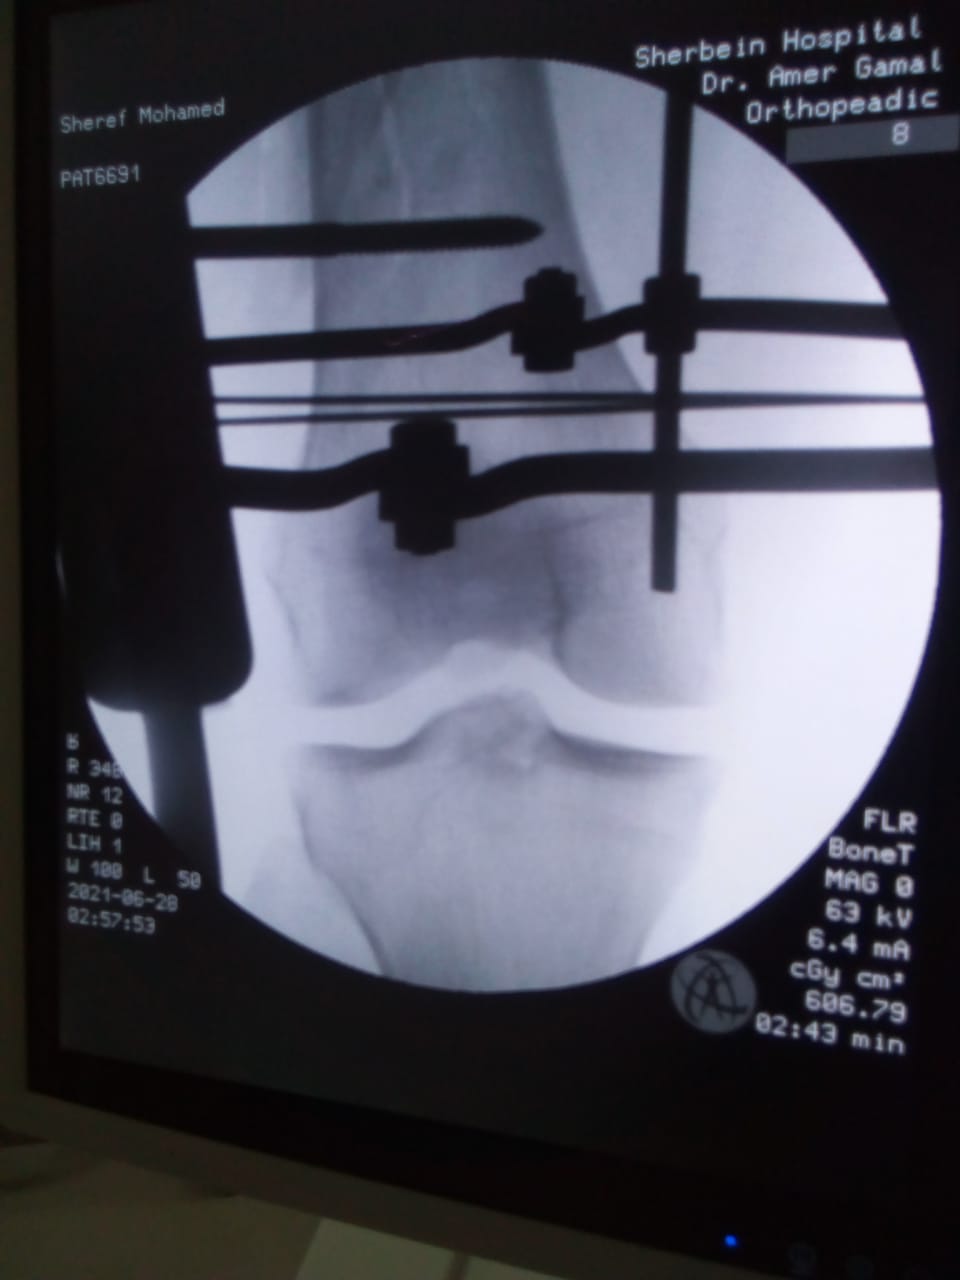

أعلن الدكتور سعد مكي، وكيل وزارة الصحة بالدقهلية، مساء اليوم، نجاح فريق طبي في إجراء تدخل جراحي دقيق لشاب يعاني من كسر مضاعف من الدرجة الثالثة إثر طلق ناري أدى إلى تهتك بالأنسجة وكسور متفتتة بالفخذ.

وتمكن الفريق الطبي من إجراء الجراحة عن طريق جهاز الليزاروف في واحدة من عمليات العظام الكبرى بمستشفى شربين المركزي، وهي تعد من العمليات المتقدمة ذات المهارة الخاصة.